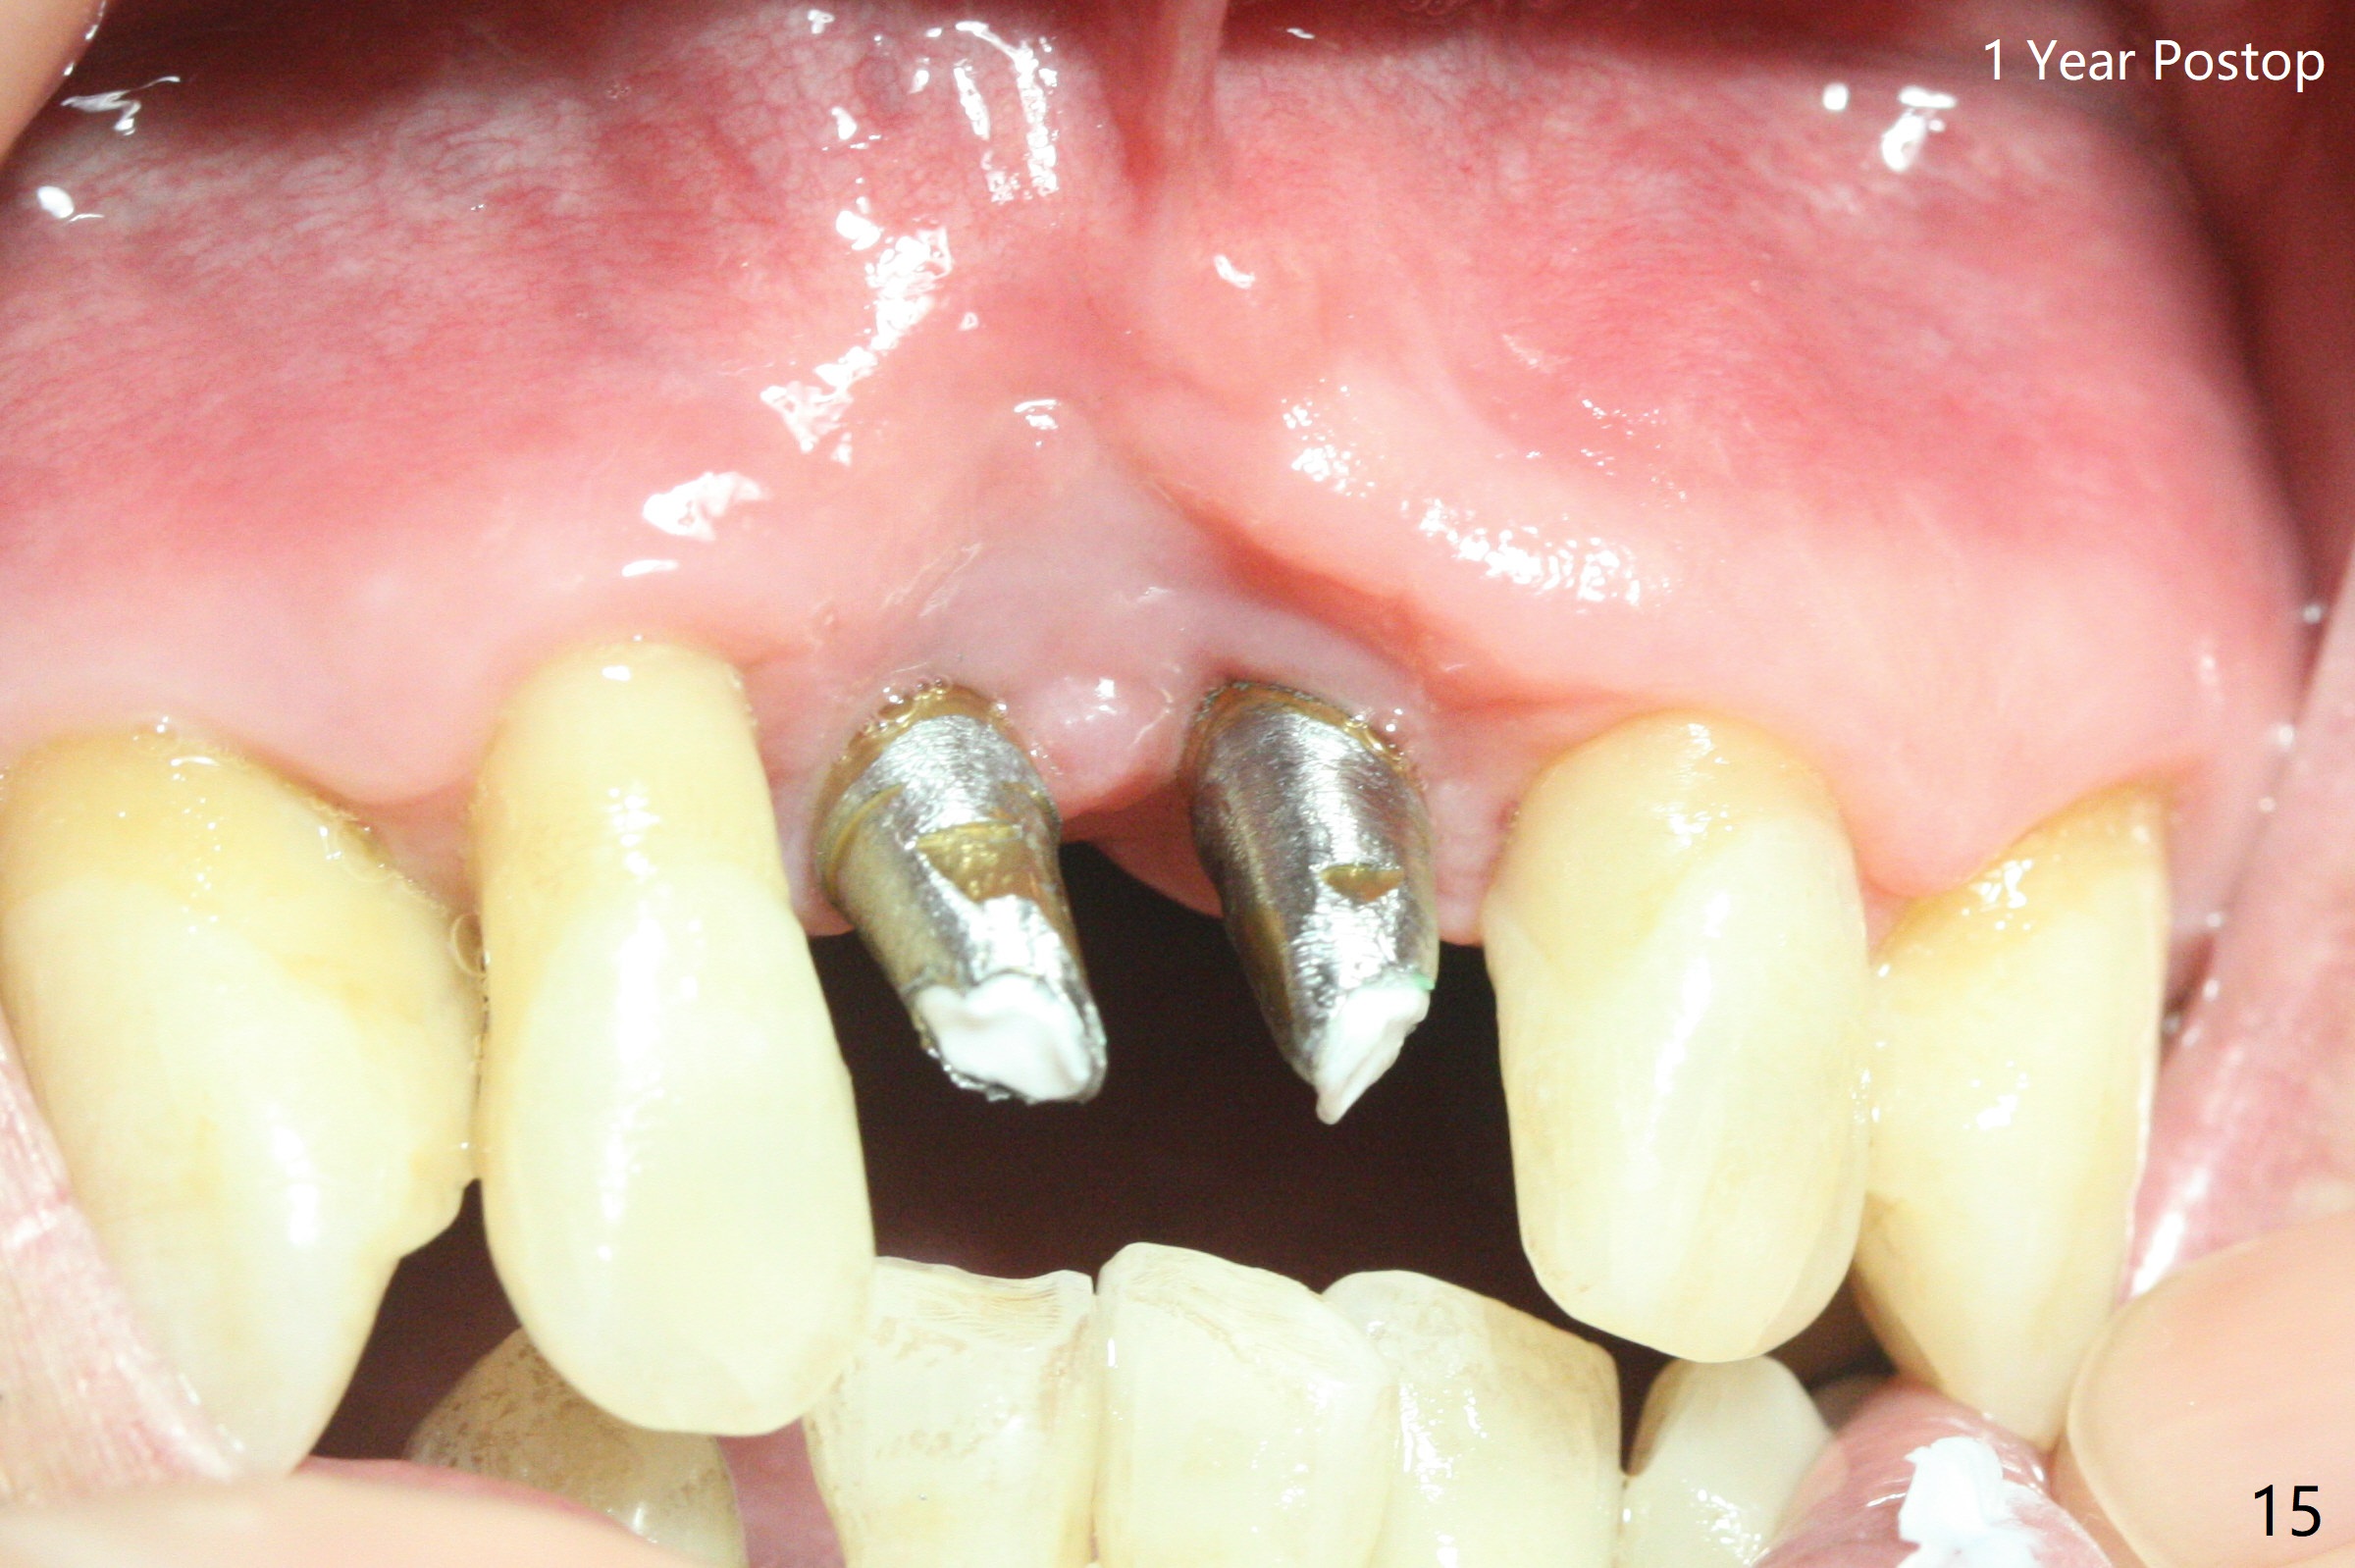

The gingiva remains recessive at #8 and 9 six months post immediate implant placement with bone graft (Fig.1). The buccal plate at #8 is particularly concave before (Fig.2 *) and after (Fig.3) abutment removal. The bony defect repair is assisted by placing a 4 mm tenting screw between the 2 implants (Fig.4) and placing allograft mixed with PRF (as putty) around the screw (Fig.5 (after replacement of the abutments)). The buccal contour improves because of the tenting screw and the bone graft placement (Fig.6 (as well as PRF and 6-month membranes)). The wound dehisces 12 days postop and immediately before leaving country for months (Fig.7). The sutures are removed, Osteogen plug is inserted (Fig.8) and periodontal dressing is applied (Fig.9). PA is taken to show the tenting screw (Fig.10 T). The latter is exposed 3 months postop (Fig.11,12). It appears that gingival graft is a must (Fig.13). Make a palatal stent, remove the temp with abutments and create a bleeding surface before harvesting a large piece of tissue. Connective tissue graft is done 5 months post bone graft (Fig.14). In fact there is no implant thread exposure. In fact the connective tissue graft does not survive. The abutments are re-prepared for pink porcelain (Fig.15). The bone loss is stable 1 year post cementation in spite of incomplete abutment seating (Fig.16). The soft tissue is nearly normal (Fig.17).